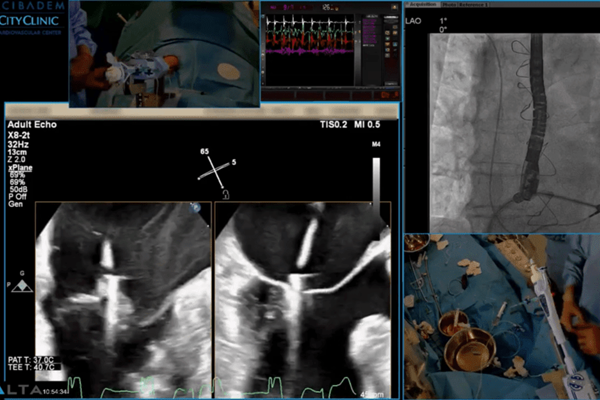

Отделението разполага с 3 ангиографски зали, напълно оборудвани за извършване на целия спектър ендоваскуларни процедури. Звеното е оборудвано със специална апаратура за вутресъдова анатомична (IVUS, OCT) и функционална оценка (FFR) на сложна съдова патология (както коронарна, така и некоронарна). Палитрата от ендоваскуларни възможности е подкрепена от най-авангардните вътресъдови методики за отнемане на фиброзна, калциева и тромбсъдържаща стентотична плака:

Екипът на отделението има дългогодишен опит в ендоваскуларното лечение на целия спектър сърдечни и сърдечни-съдови заболявания. В Acibadem City Clinic УМБАЛ Витоша се провежда едноваскуларно лечение освен на коронарна патология, лечение на структни заболявания на сърцето като клапни пороци (аортна стеноза, митрална инсуфициенция) чрез имплантация на транскатетърна аортна клапа (TAVI), имплантация на MitraClip и лечение на вродени сърдечни малформации чрез имплантация на оклудер или друг тип устройства.